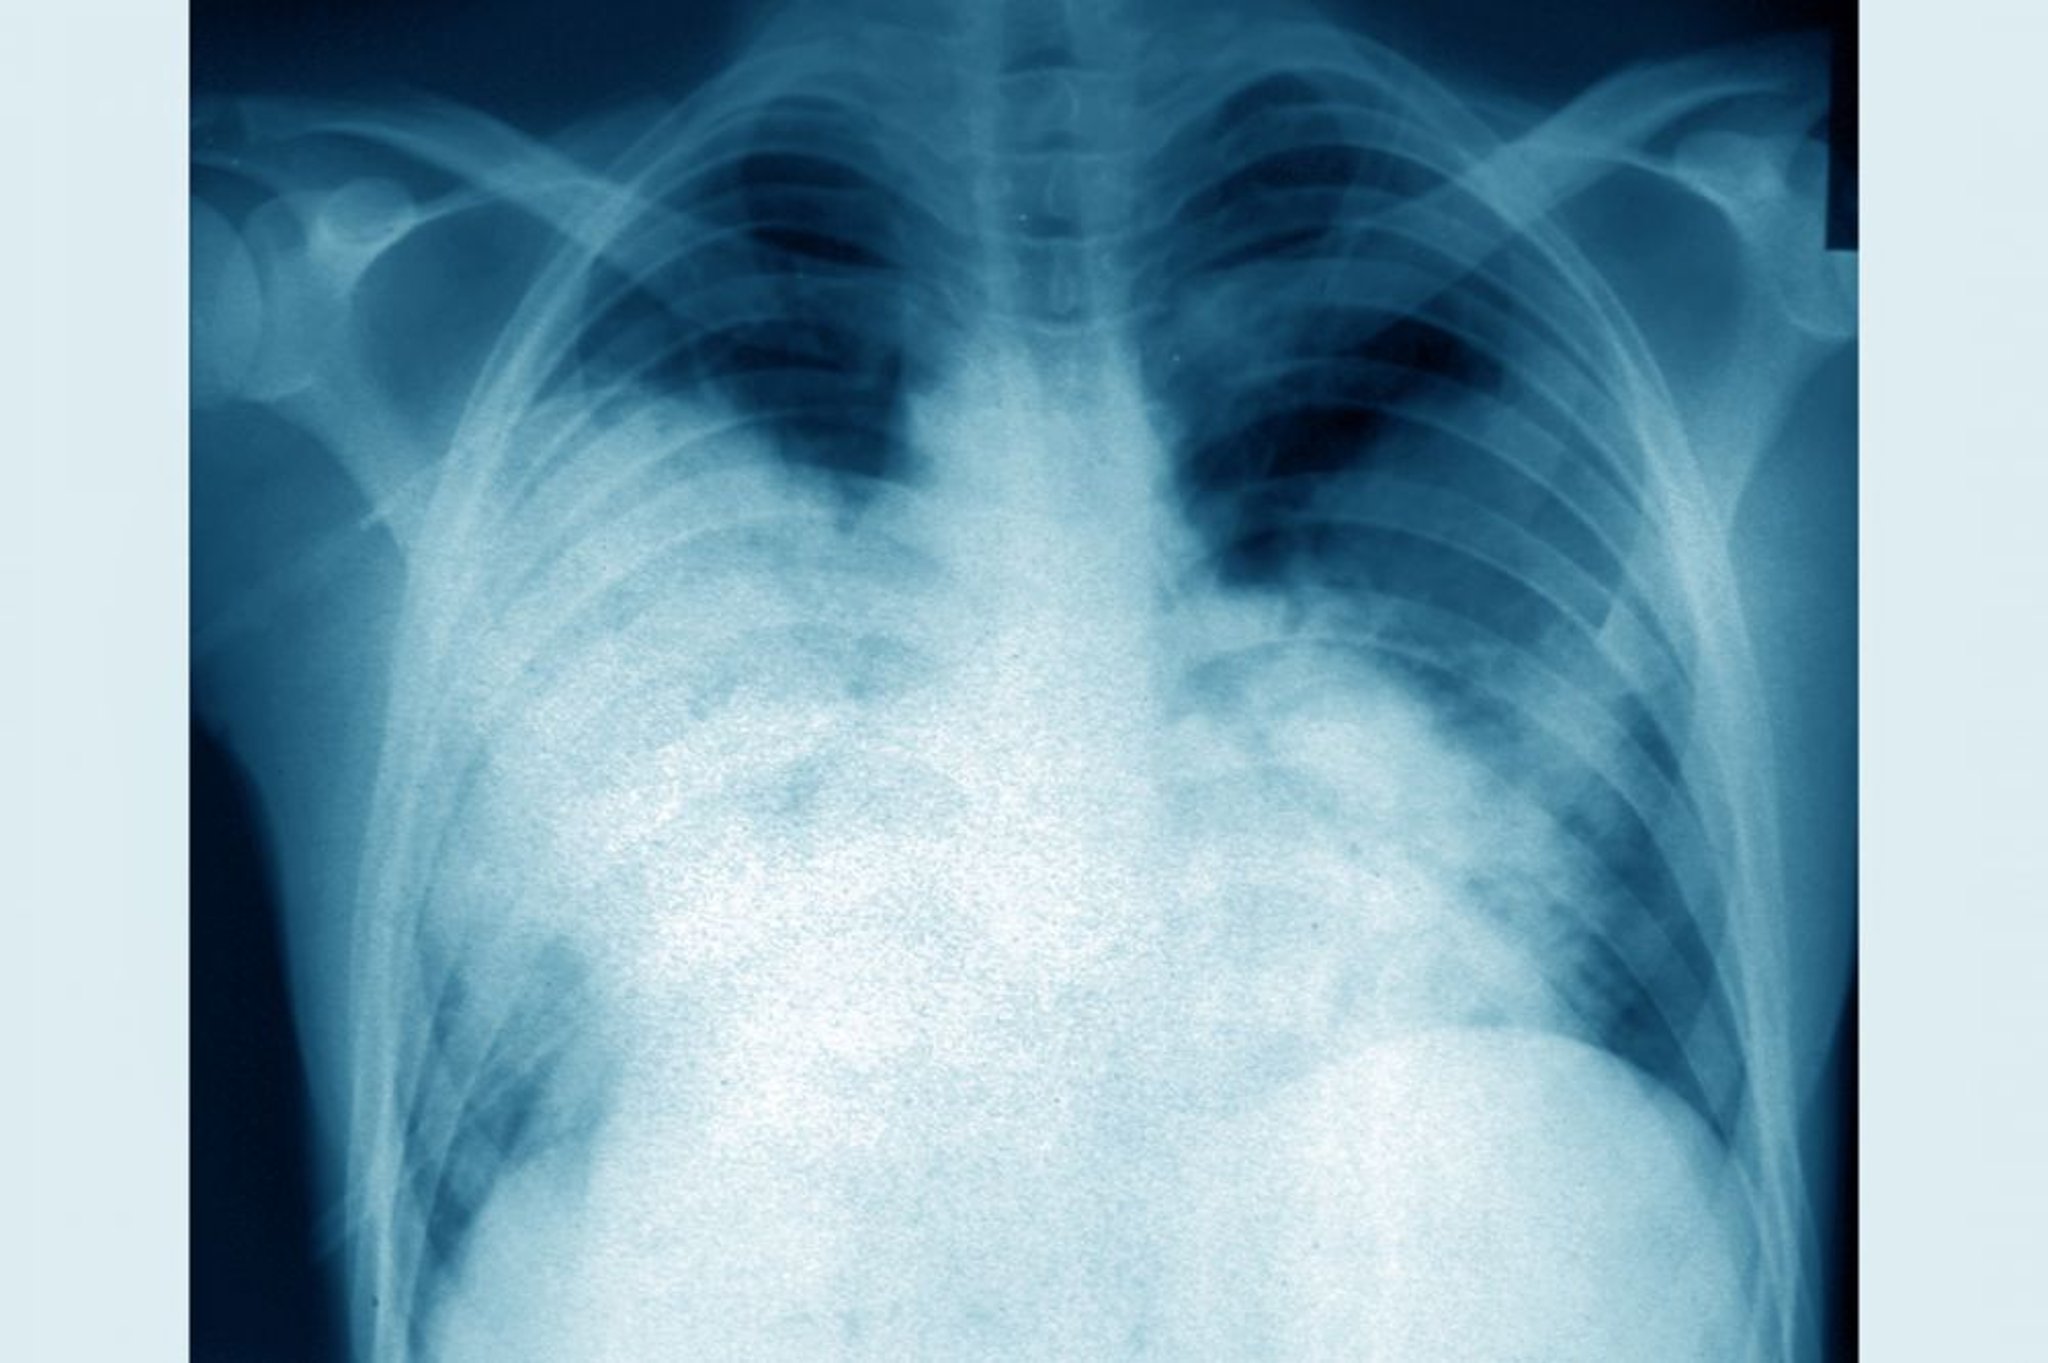

Légionellose (radiographie thoracique)

Cette radiographie thoracique frontale montre une pneumonie bilatérale aiguë (maladie du légionnaire causée par Legionella pneumophila).